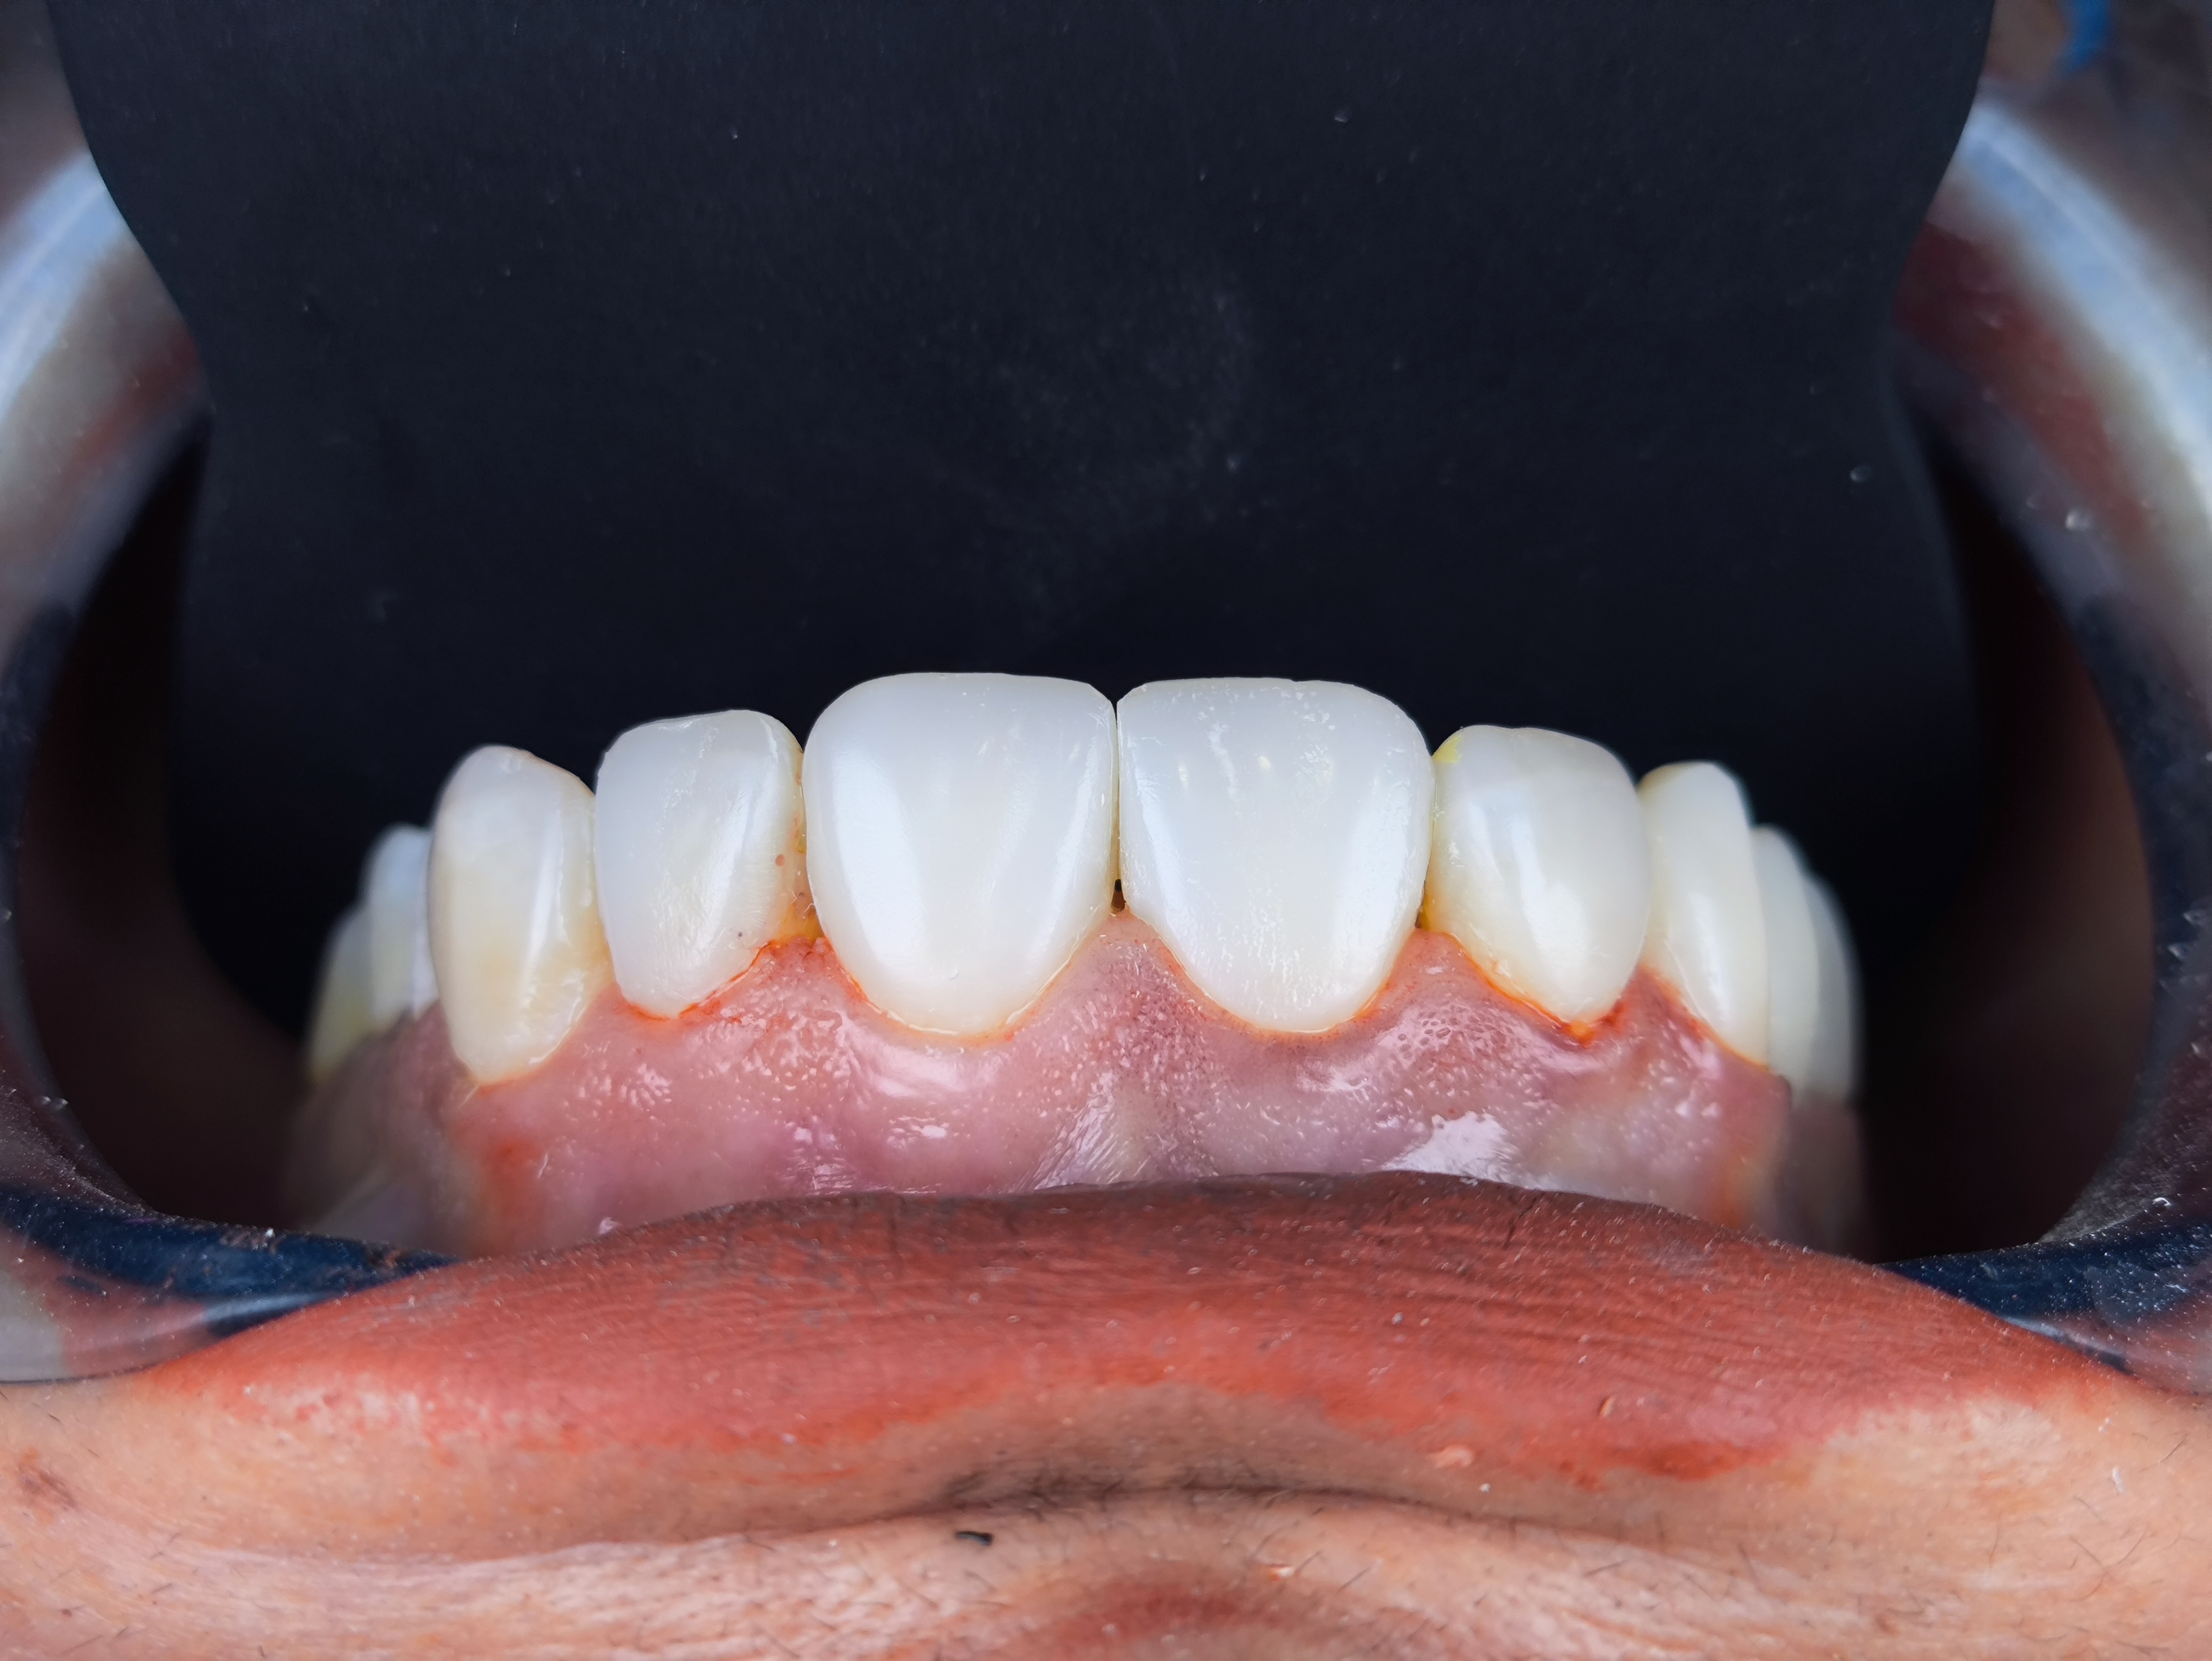

Smile Design Case 3